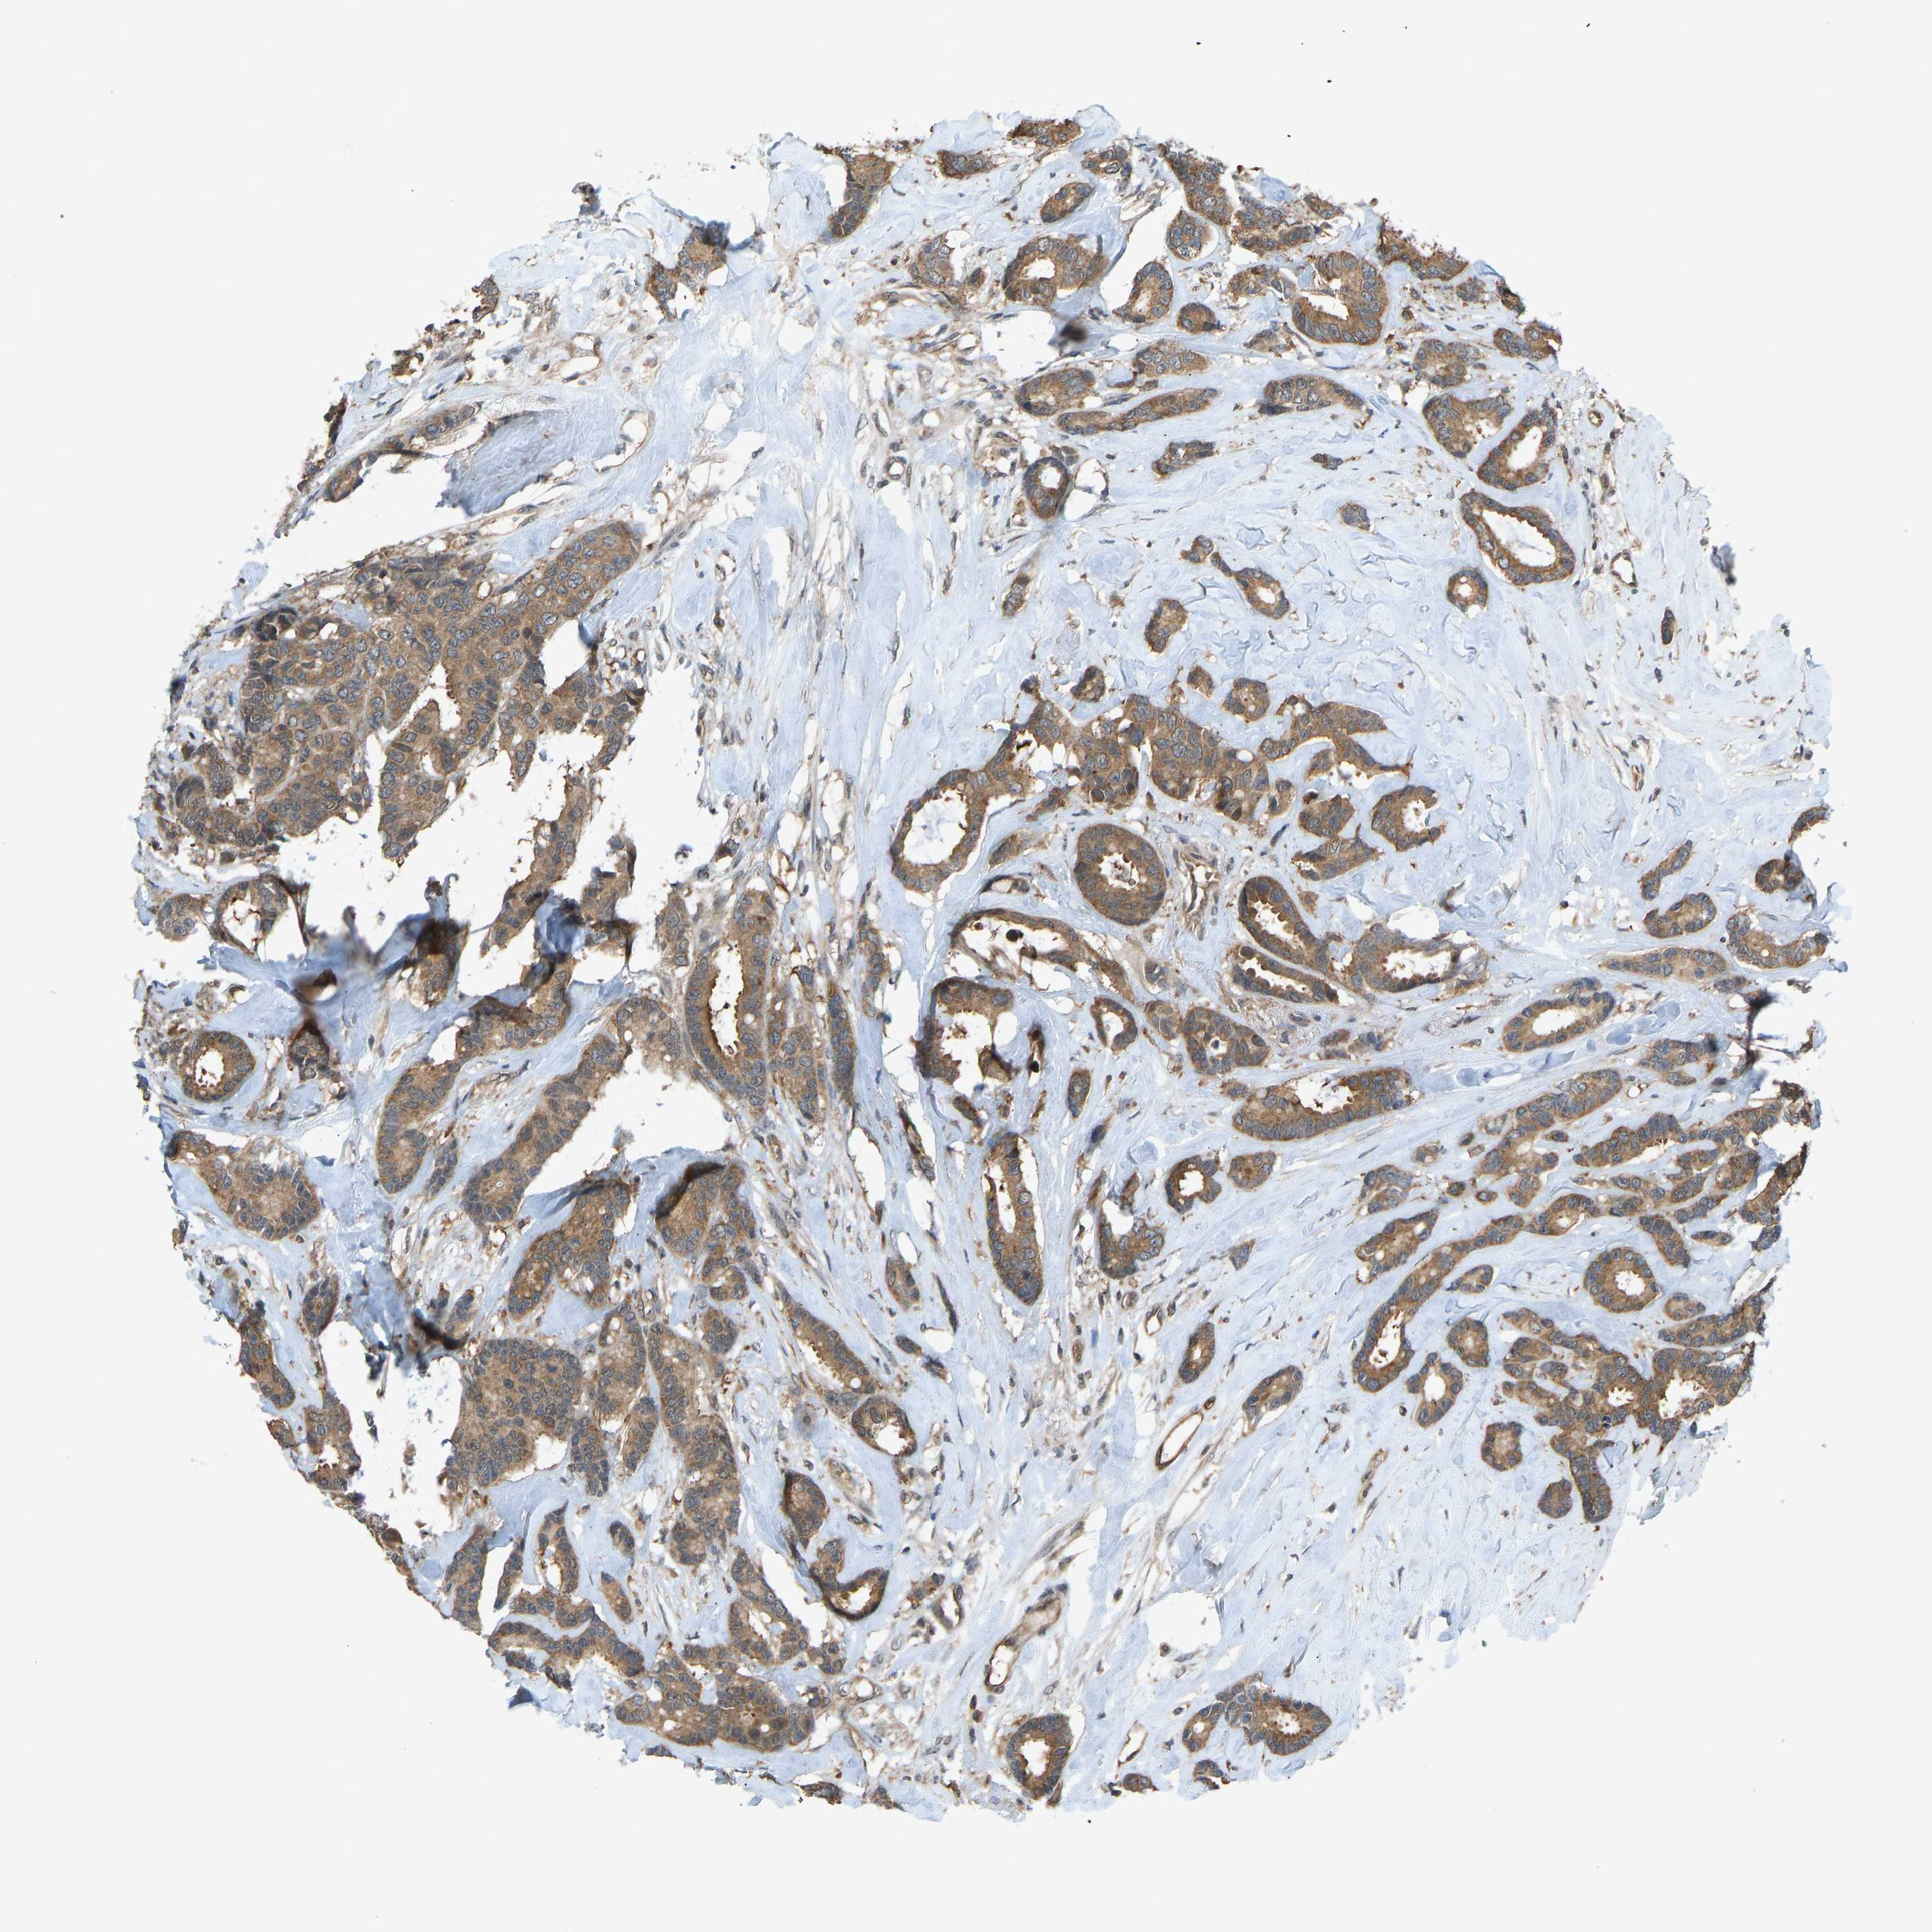

BRCA TCGA BRCA VALIDATION PROTEIN EXPRESSION